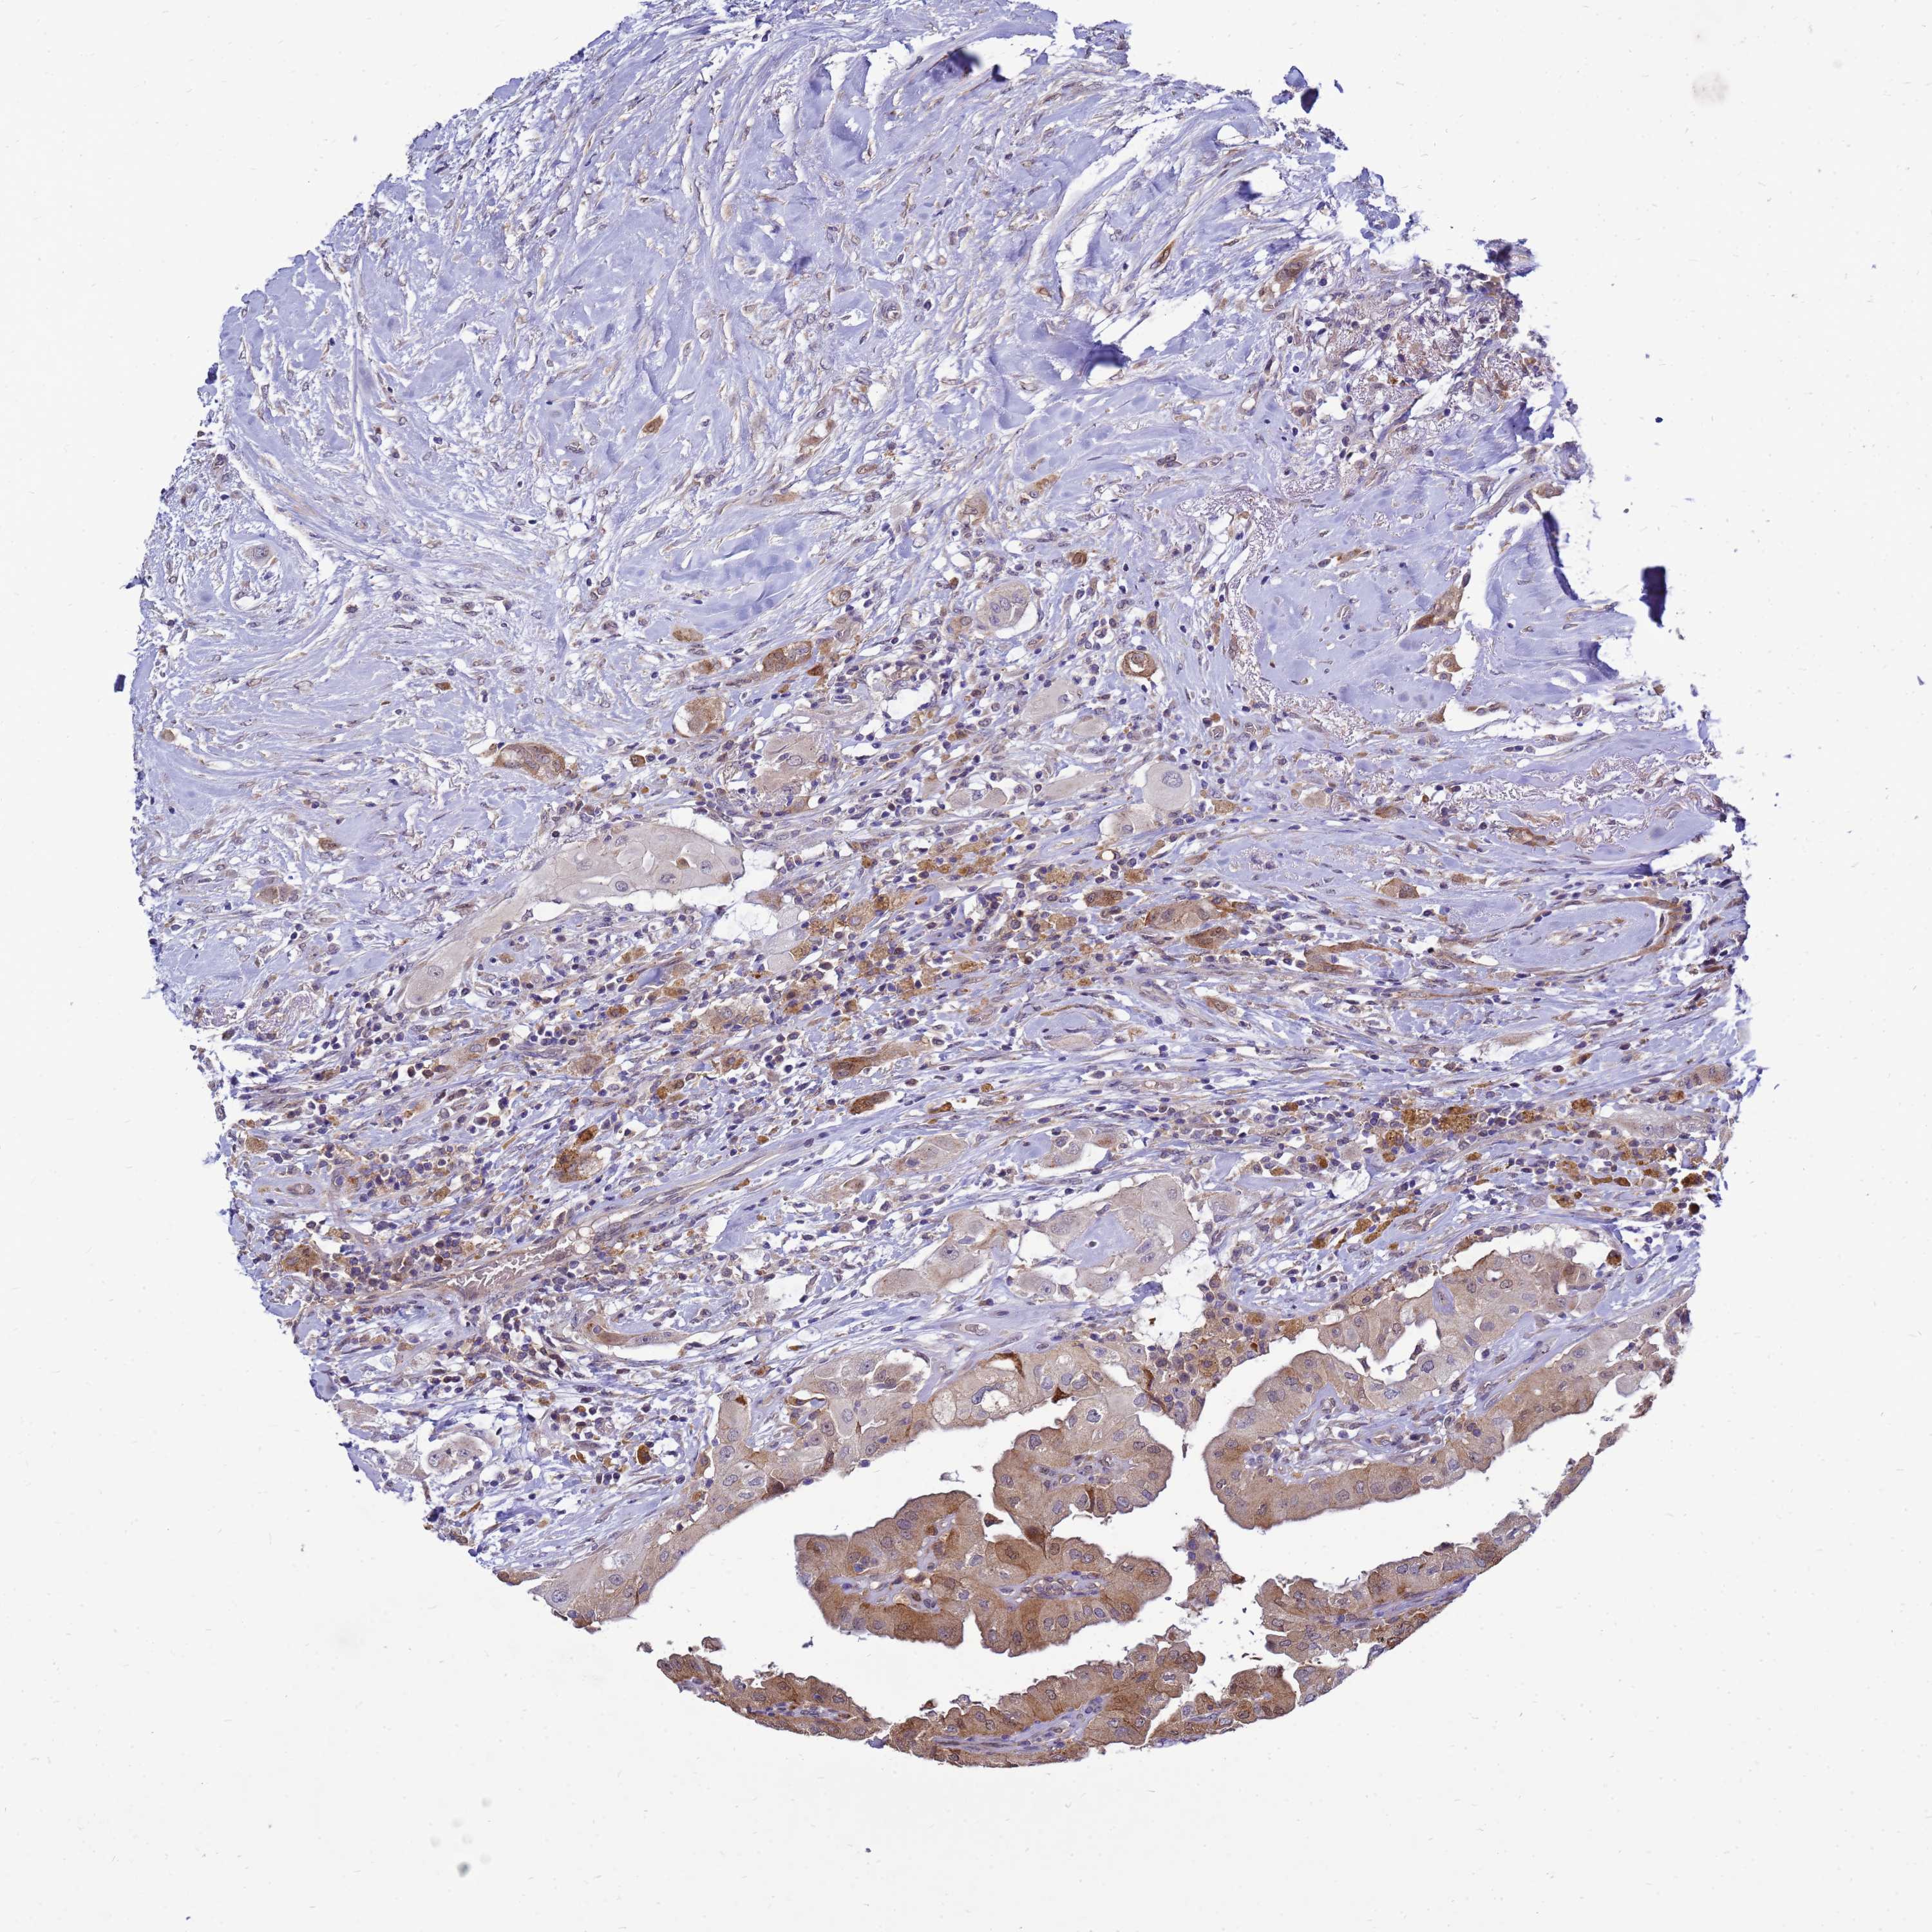

THYROID CANCER - Protein expressioni

A mouse-over function shows sample information and annotation data. Click on an image to view it in a full screen mode. Samples can be filtered based on level of antibody staining by selecting one or several of the following categories: high, medium, low and not detected. The assay and annotation is described here.

Note that samples used for immunohistochemistry by the Human Protein Atlas do not correspond to samples in the TCGA dataset.

Antibody stainingi

Antibody staining in the annotated cell types in the current human tissue is reported as not detected, low, medium, or high, based on conventional immunohistochemistry profiling in selected tissues. This score is based on the combination of the staining intensity and fraction of stained cells.

Each image is clickable and will lead to virtual microscopy that enables deeper exploration of all samples and also displays staining intensity scores, fraction scores and subcellular localization as well as patient and tissue information for each sample.

Antibody HPA045537

Papillary adenocarcinoma, NOS

Follicular adenoma carcinoma, NOS